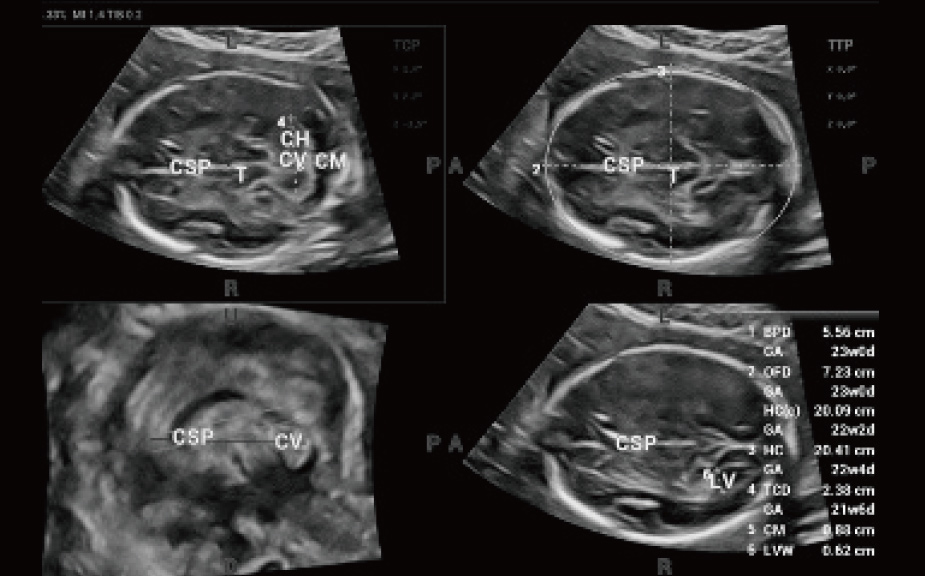

Scenario-oriented Full-stack Intelligence

The innovative Smart Scene 3D solution enables automated identification of tissue characteristics and delivers organ-specific diagnosis with full-stack intelligence throughout the entire procedure. This innovation reduces dependence on clinical skills, while elevating diagnostic accuracy, confidence, and efficiency.